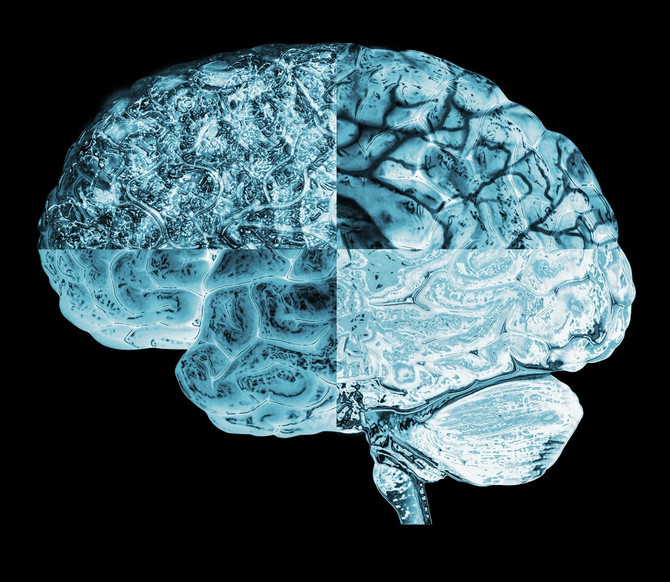

Nalazi ukazuju na to da strukturalne promjene u mozgu tokom menstruacije najvjerovatnije nisu ograničene samo na one regije povezane s menstrualnim ciklusom. “Ovo su prvi rezultati o simultanim promjenama u mikrostrukturi moždane bijele tvari i debljini moždane kore koje se podudaraju s hormonskim ritmovima menstrualnog ciklusa”, pišu naučnici.

Utvrdili su da se mikrostruktura bijele tvari, masne mreže neuronskih vlakana koja prenose informacije između regija sive tvar, mijenja s hormonalnim promjenama, uključujući pubertet, korištenjem oralne kontracepcije i hormonske terapije, piše Science Alert.

Naučnici su proveli MRI skeniranje ispitanica tokom tri menstrualne faze: menstruacije, ovulacije i srednje luteinske faze. Pritom su im mjerili i nivo hormona. Rezultati su pokazali da se, kako hormoni fluktuiraju, mijenjaju i volumeni sive i bijele tvari, kao i volumen cerebrospinalne tekućine.

Konkretno, neposredno prije ovulacije kod ispitanica je primijećena promjena u bijeloj tvari, što ukazuje na brži prijenos informacija. Folikulostimulirajući hormon, koji raste prije ovulacije i pomaže stimulirati folikule jajnika, bio je povezan s debljom sivom tvari. Progesteron, čiji nivo raste nakon ovulacije, povezan je pak s povećanjem tkiva i smanjenim volumenom cerebrospinalne tekućine,piše Vijesti